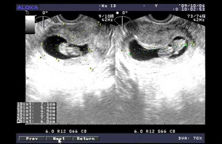

3D微控超導介入技術,運用聲像、影像三維掃描功能的導航設備,可將卵巢部位及囊腫部位立體成像顯示,由微控工作平台的專業手術醫師將細如髮絲的微超導電極送入卵巢囊腫囊腔內,精確地吸出囊內積液,再由微控介入治療系統將遏制囊腫再生的藥物直接介入囊腫處,通過藥物作用,使囊腫病灶組織細胞核抑制、失活,囊壁上皮組織失活,達到治癒囊腫的目的,並使卵巢結構和功能恢復正常。技術原理

超導“消融刀”不是真正意義上的手術刀,它擁有多支帶有溫差電偶的超導針,由計算機全程監控,在B超的動態觀察和引導下,通過探頭將射頻治療源經過組織腔道,準確定位介入到人體局部的病變部位,自動精確地控制其治療功率、時間和治療範圍,使病變局部組織產生生物高熱效應,然後使組織發生凝固、變性和壞死,從而腫瘤,最後被正常組織吸收或自動排出。技術優勢